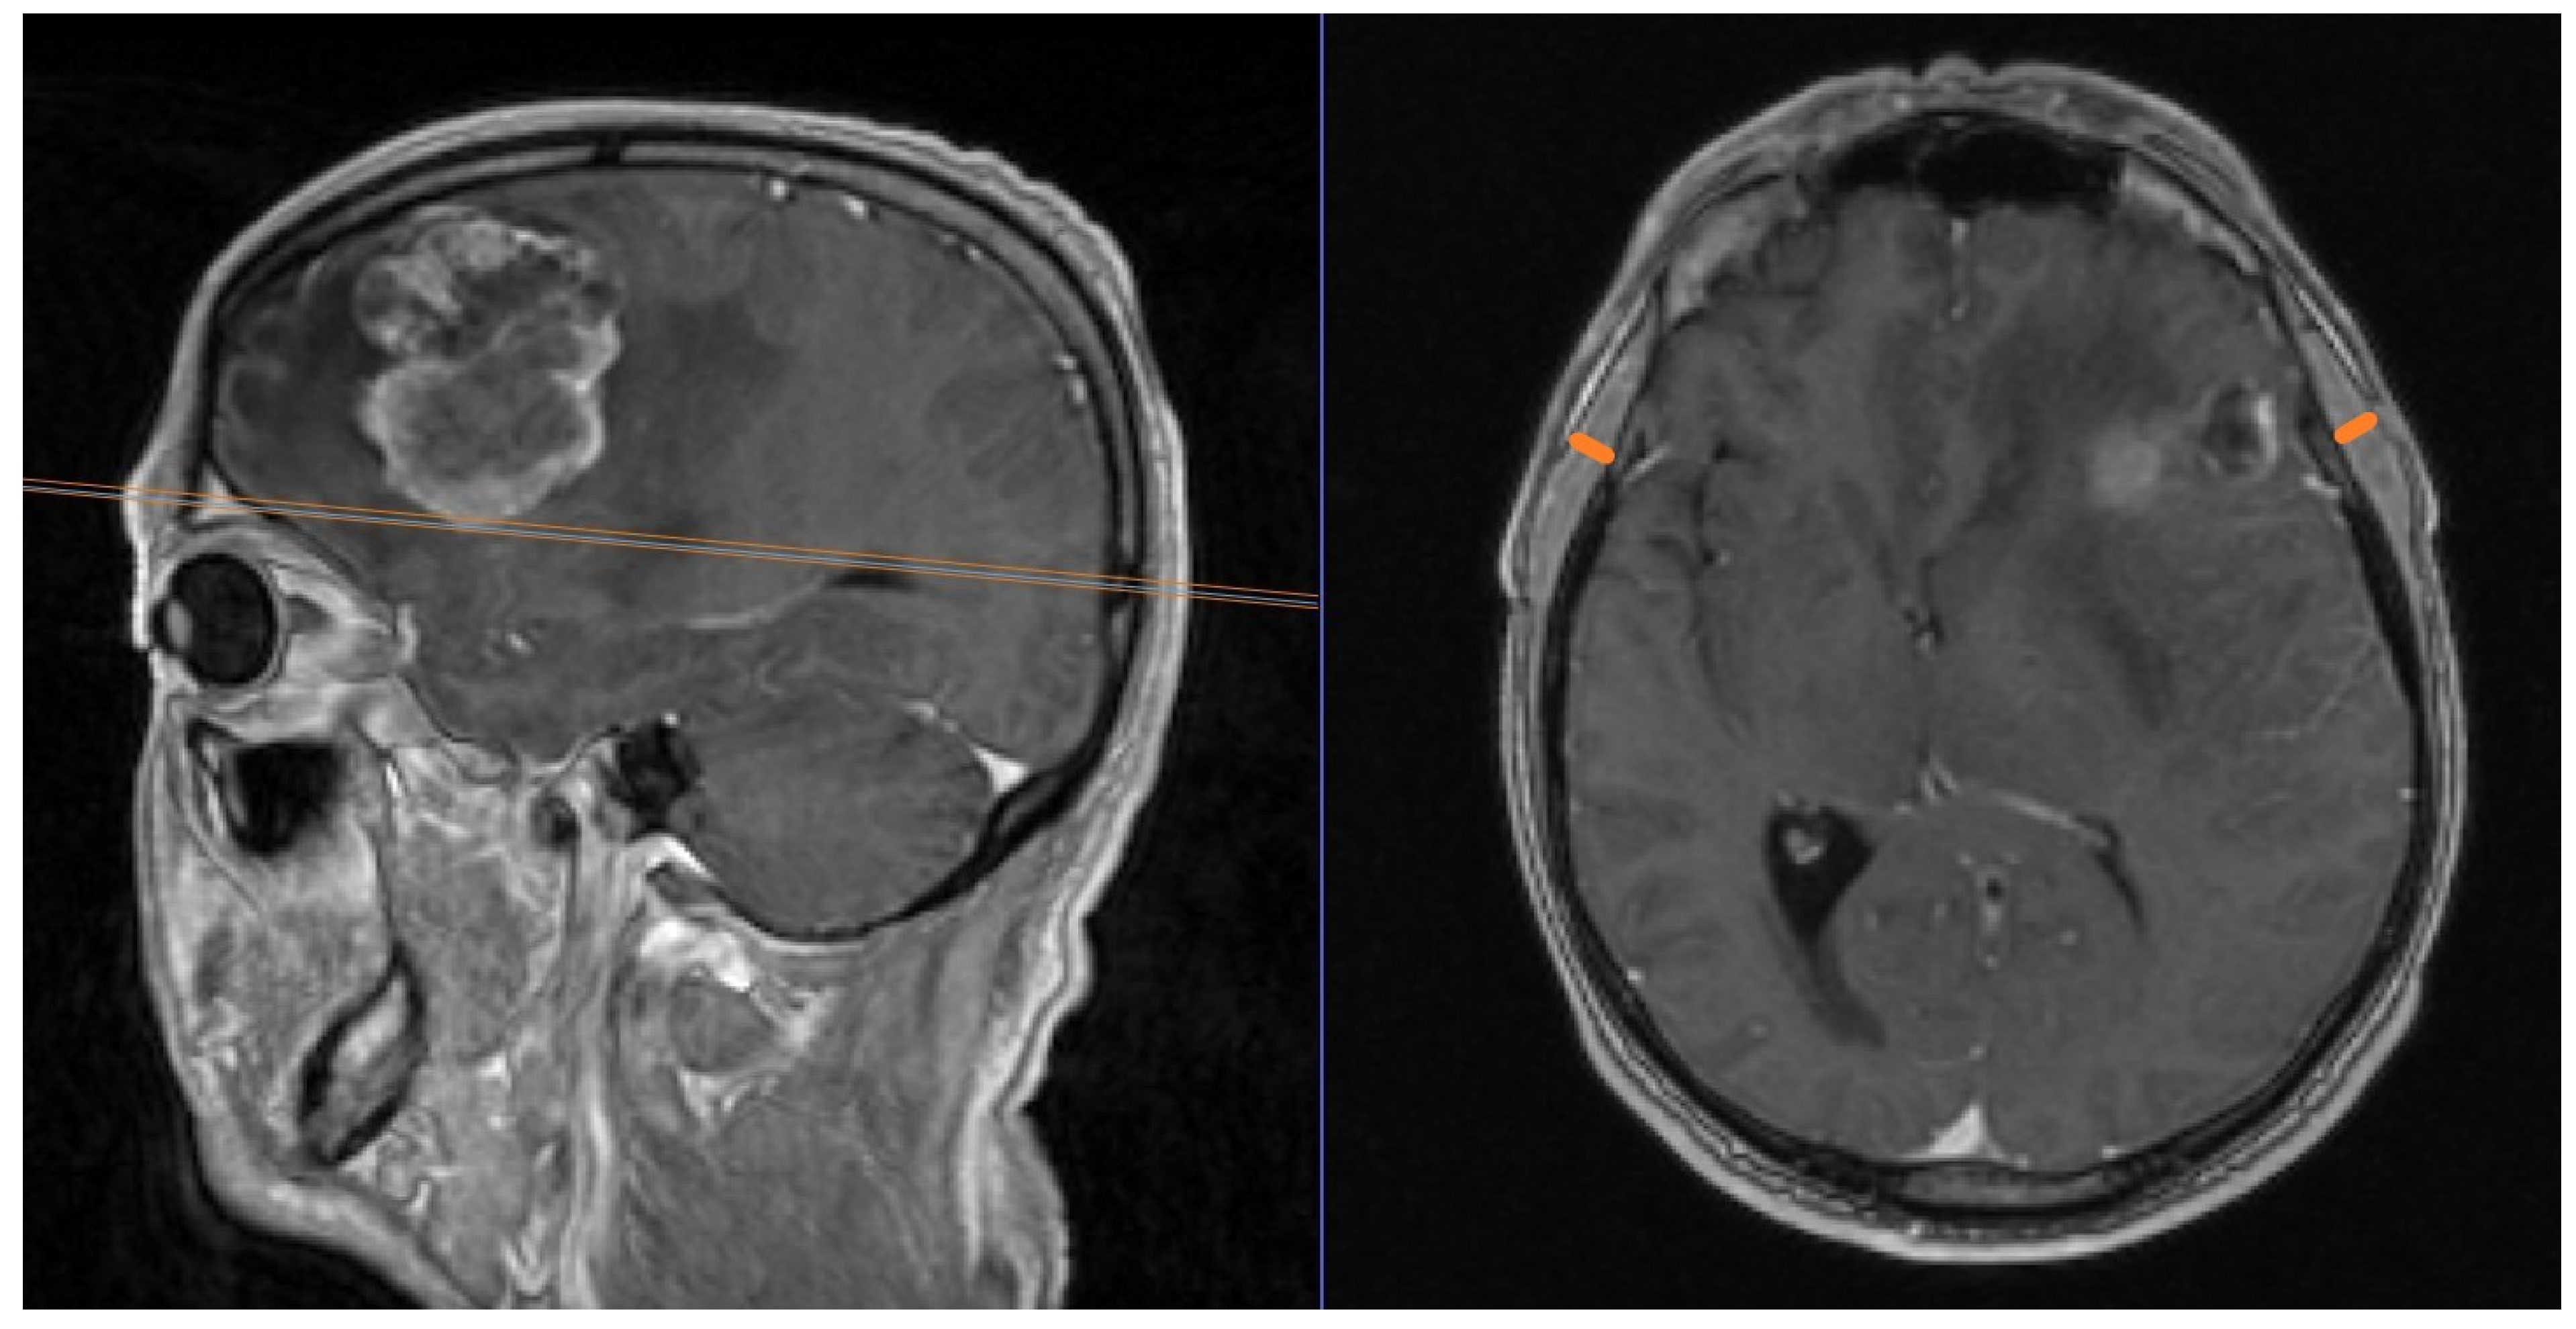

Patients undergoing a resection of 1–3 brain metastases in our institution were included. Surgical decisions were taken according to the interdisciplinary neuro-oncology tumor board. Only surgical patients were included. In a retrospective approach, TMT was measured using previously published protocols [4]: in the preoperative MRI scan, measurements were taken in axial images of contrast-enhanced T1-weighted scans. The orbital roof served as a landmark for cranio-caudal orientation, which was verified in the sagittal plane. For fronto-occipital orientation, the Sylvian fissure was used. There, we measured the temporal muscle from the inner to the outer margin, whilst its fascia was meticulously excluded from measurements. Bilateral measurements of TMT were performed and the mean was calculated. In postoperative measurements of patients with a history of surgical temporal muscle dissection, we performed exclusively unilateral measurements of the non-dissected side. An example of a TMT measurement is shown in Figure 2.

Figure 2.

TMT measurement in a patient from our cohort with a left frontal brain metastasis. Sagittal and axial T1 contrast-enhanced images are shown. The orange lines on the axial image depict the measurement of TMT.